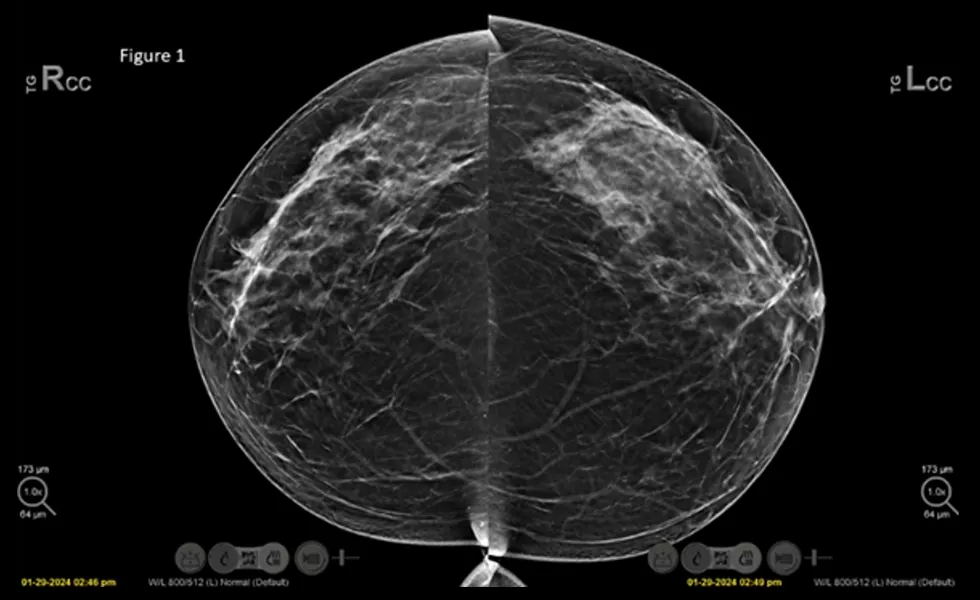

X-ray image

As published in the clinical review, the left image view shows no abnormalities bilaterally, while the right image reveals an area of concern marked by the Genius AI Detection, with a case score of 87% and flagged as high priority.